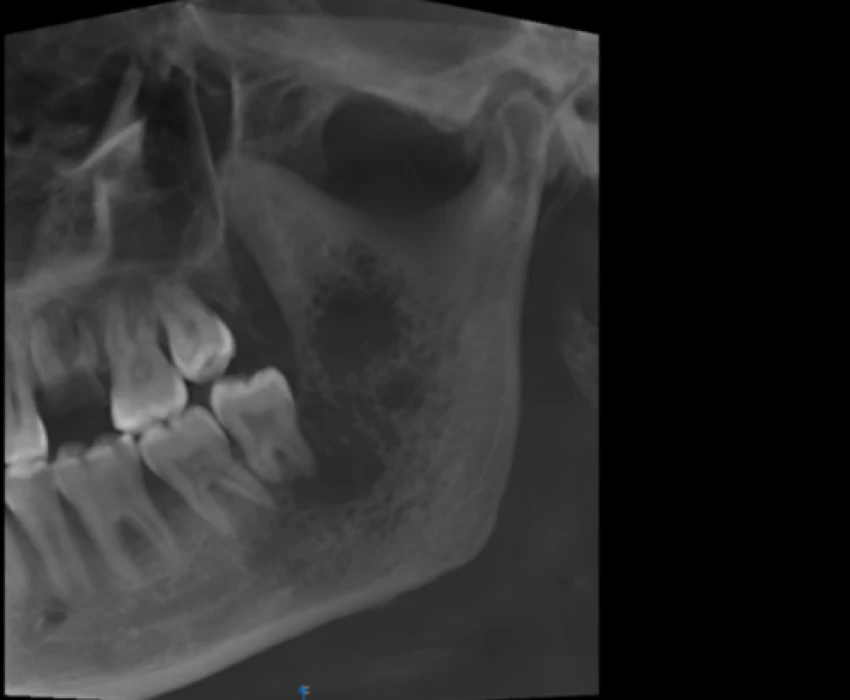

A patient reported to our department with a chief complaint of pain in lower left back region of jaw since 1 month and diagnosed as Carcinoma Involving Left Mandibular Buccal Vestibule and Alveolus Extending Upto Ramus and was treated for the same.

Surgical management was done.